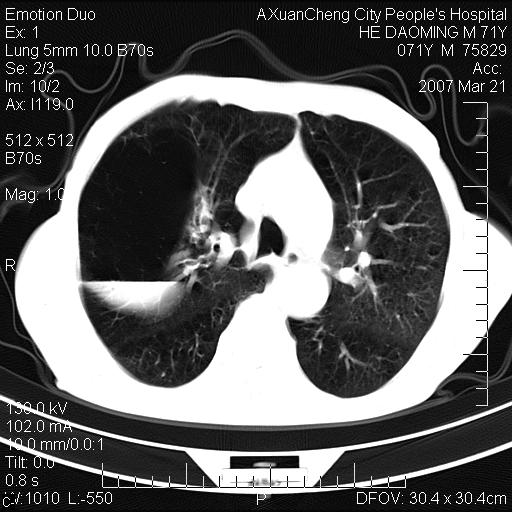

右侧相当于叶间软组织样密度ct值约50hu,请大家讨论是什么性者病变

考虑:慢性支气管炎合并全小型肺气肿、肺大泡、间质纤维化、感染,右斜裂积液。

考虑慢支,肺气肿,肺大泡,间质纤维化;右侧斜裂液气胸考虑(可能因为肺大泡破裂破入斜裂所致).

考虑:慢性支气管炎合并右侧全小型肺气肿、肺大泡并感染、双肺间质纤维化,右斜裂积液。

如果患者变化一下体位扫描可分辨液平与斜裂的关系。